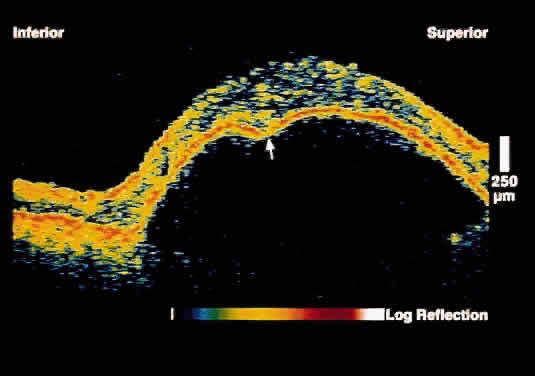

Serous Macular Detachment Secondary to Optic Nerve Pit Optical coherence tomography images of this clinical entity clearly demonstrate

the relation between the optic nerve pit and serous macular detachment (Fig. 4). These images support the concept that fluid from the optic pit directly

enters the neurosensory retina and not the subretinal space.13  Fig. 4. OCT image through macula and optic disc in a patient with an optic nerve

head pit. The optic pit is contiguous with a schisis-like cavity in

the inner retina and not with the subretinal space. Fig. 4. OCT image through macula and optic disc in a patient with an optic nerve

head pit. The optic pit is contiguous with a schisis-like cavity in

the inner retina and not with the subretinal space.